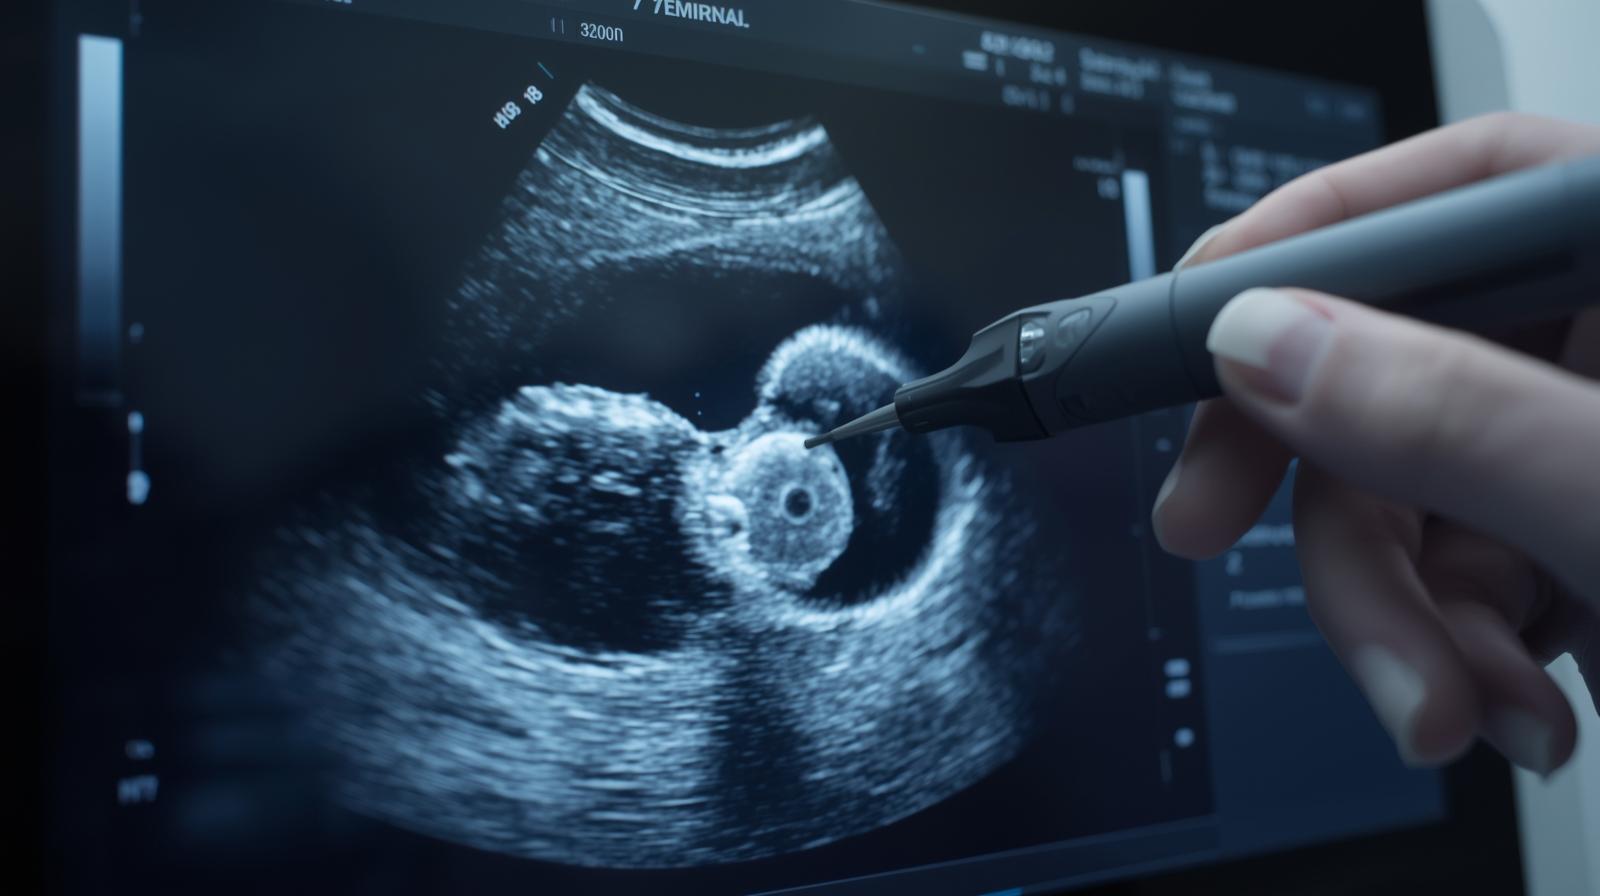

Hamileliğin 7. haftası, gebeliğin ilk trimesterinde çok kritik bir döneme girildiği anlamına gelir. Bu hafta ile birlikte anne adayının vücudu hormonların etkisiyle belirgin değişimler yaşarken, embriyo da hızla gelişmeye devam eder. Artık ultrasonda kalp atışlarının duyulabilmesi mümkündür ve bebekte organ gelişimi hız kazanır. Bu içerikte 7. hafta hamilelik belirtileri, bebeğin gelişimi, beslenme önerileri ve dikkat edilmesi gereken noktaları detaylıca ele alıyoruz.

Kalbi düzenli atmaya başlamıştır ve ultrason sırasında dakikada 120–160 arasında kalp atışı duyulabilir.

İlk muayenede genellikle ultrason ile gebelik kesesi ve embriyo kalp atışı kontrol edilir.

Evet, vajinal ultrason ile embriyo ve kalp atışı genellikle görülebilir.